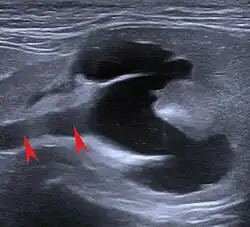

Ultrasound image of hydronephrosis in a cat. The arrows point to the dilated ureter.

The main symptoms of chronic kidney disease in cats are lack of appetite (anorexia), increased drinking (polydipsia), increased urine output (polyuria), fatigue (apathy), vomiting and weight loss. In addition, diarrhea, inflammation of the oral mucosa (stomatitis) with the formation of ulcers (ulcera), increased salivation (hypersalivation) and bad breath may occur as a result of uremia. Increased blood pressure (arterial hypertension) with damage to the eye (fundus hypertonicus, hypertensive retinopathy), anemia (anemia), itching, dehydration, soft tissue calcifications, bleedings and accumulation of water in the tissues (oedemas) are also more frequent accompanying symptoms. In the case of severe uremia, neurological neurology manifestations such as apathy, seizures, delirium, coma, abnormal movements and muscle disorders (myopathys).[10] Typically, the symptoms—in contrast to acute renal failure—occur gradually over weeks, months or even years, and the general condition is poor. In addition, acute kidney failure is initially characterized by reduced urine production. However, an existing mild or moderate chronic kidney disease is often suddenly worsened by an acute event ("exacerbation") and thus becomes conspicuous to the cat owner. This can be the case, for example, if one kidney has already become a non-functioning shrunken kidney due to urinary retention and the second suddenly swells acutely due to urinary retention (hydronephrosis) and is damaged ("large kidney-small kidney syndrome") or if hyperthyroidism is treated and the glomerular filtration rate is suddenly reduced as a result.[17]

The ultrasound examination allows morphological changes in the kidneys in more detail. In addition to changes in size and shape, renal cysts, localized (focal) organ damage, water sac kidneys and urinary retention as well as tumors can also be visualized. Hardly defined (diffuse) organ changes are accompanied by changes in echogenicity, but can only rarely be assigned to defined diseases.[22] Pulsed Wave Doppler" can also be used to detect circulatory disorders.[23] Calcification (nephrocalcinosis) is also common in chronic kidney disease and can also be detected sonographically.[24]